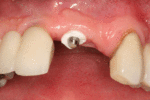

For individual tooth replacement, an implant abutment is first secured to the implant with an abutment screw. A crown (the dental prosthesis) is then connected to the abutment with dental cement, a small screw, or fused with the abutment as one piece during fabrication.[6](pp211–232) Dental implants, in the same way, can also be used to retain a multiple tooth dental prosthesis either in the form of a fixed bridge or removable dentures.

Recovery

The prosthetic phase begins once the implant is well integrated (or has a reasonable assurance that it will integrate) and an abutment is in place to bring it through the mucosa. Even in the event of early loading (less than 3 months), many practitioners will place temporary teeth until osseointegration is confirmed. The prosthetic phase of restoring an implant requires an equal amount of technical expertise as the surgical because of the biomechanical considerations, especially when multiple teeth are to be restored. The dentist will work to restore the vertical dimension of occlusion, the esthetics of the smile, and the structural integrity of the teeth to evenly distribute the forces of the implants.[6](pp241–251)

Prosthetic procedures for single teeth, bridges and fixed dentures

An abutment is selected depending on the application. In many single crown and fixed partial denture scenarios (bridgework), custom abutments are used. An impression of the top of the implant is made with the adjacent teeth and gingiva. A dental lab then simultaneously fabricates an abutment and crown. The abutment is seated on the implant, a screw passes through the abutment to secure it to an internal thread on the implant (lag-screw). There are variations on this, such as when the abutment and implant body are one piece or when a stock (prefabricated) abutment is used. Custom abutments can be made by hand, as a cast metal piece or custom milled from metal or zirconia, all of which have similar success rates.[18](p1233)